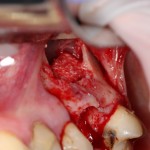

Вот ситуация:

По ряду причин, мы вынуждены удалить верхнюю шестерку и заменит ее на имплантат.

Все начинается с удаления зуба:

Обратите внимание на состояние вестибулярной стенки лунки. В проекции верхушек корней вы можете увидеть костный дефект, вызванный длительным воспалительным процессом (собственно, почему этот зуб пришлось удалять). В этом случае, вестибулярная стенка лунки неизбежно лизируется после удаления зуба, а это приведет не только к проблемам в эстетике, но и осложнит последующий уход за протетической конструкцией. Поэтому в данном случае мы должны продумать, в том числе, аугментацию лунки. И порядок действий здесь несколько иной, нежели в предыдущем случае.